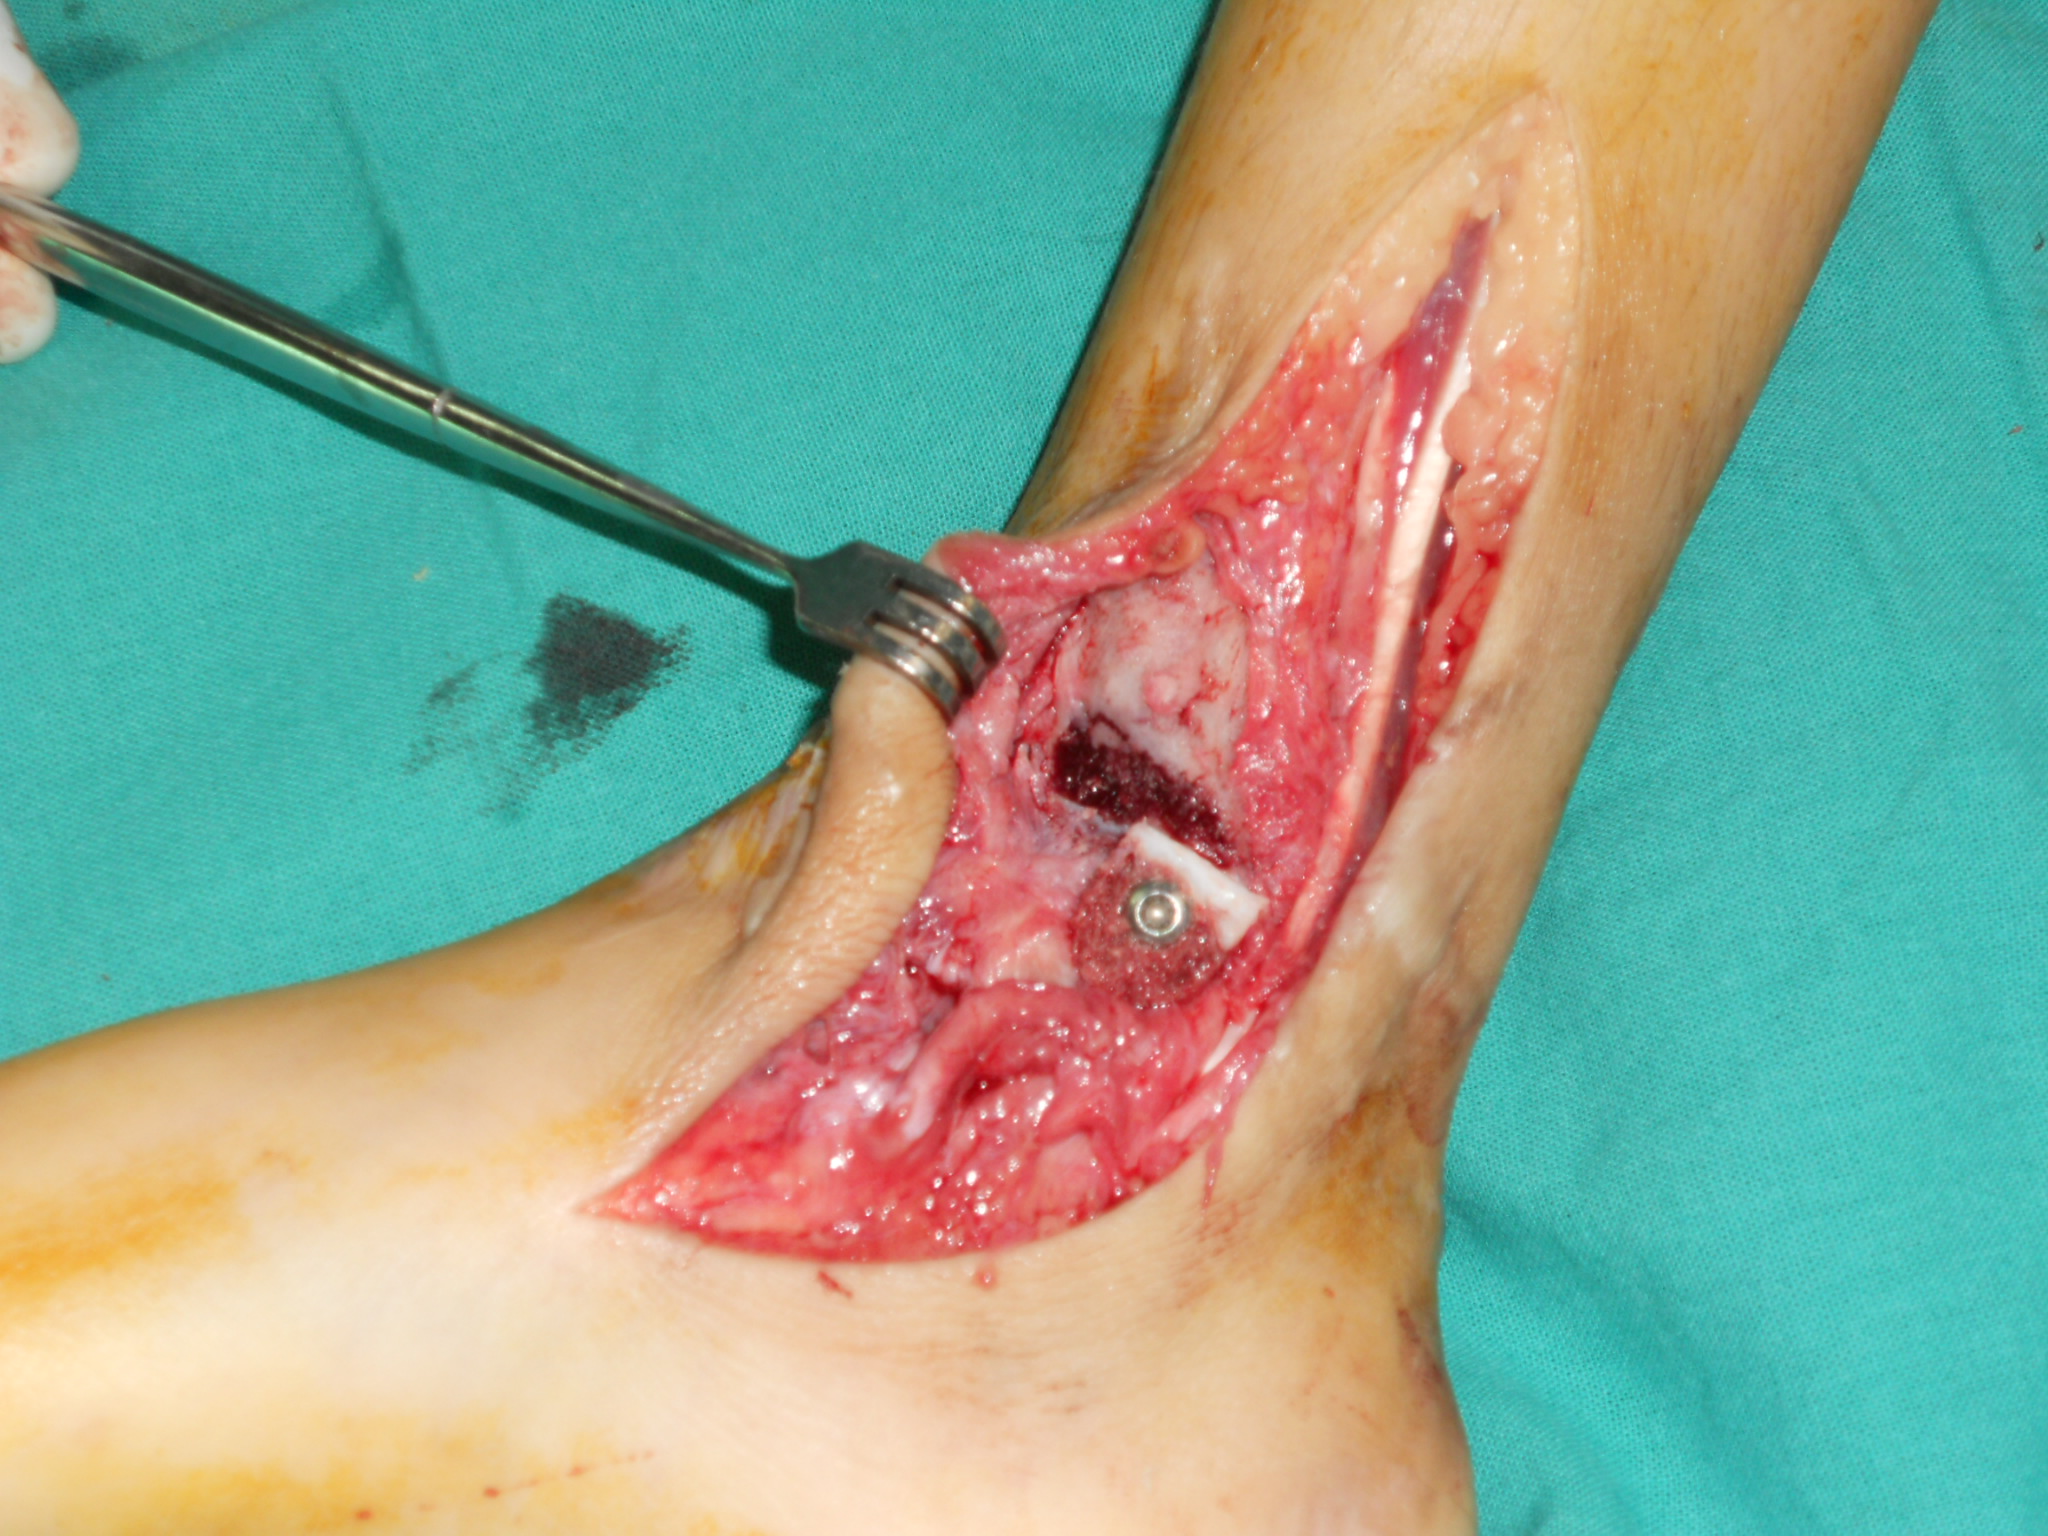

IntroducciónLas fracturas Salter-Harris VI (SHVI) son lesiones que se caracterizan por presentar ablación del anillo pericondral. Son infrecuentes en niños pero potencialmente devastadoras. El objetivo de este estudio fue evaluar el mecanismo de producción, el tratamiento y los resultados funcionales de estas lesiones localizadas en el pie y el tobillo.Material y métodosSe analizaron retrospectivamente todos los pacientes con lesiones SHVI de tobillo y pie tratadas entre Enero de 2010 y Enero de 2013. Se documentaron datos demográficos, clasificación, mecanismo de lesión, tipo de lesiones asociadas y número de cirugías que requirieron. Los pacientes fueron evaluados funcionalmente con el score de AOFAS y radiográficamente para determinar la viabilidad de la fisis, acortamiento del miembro o deformidad angular.ResultadosSe analizaron 5 fracturas en 4 pacientes (3 masculinos y 1 femenino). La edad promedio al momento de la lesión fue de 7.5 años (rango, 6 a 10 años). El seguimiento promedio fue de 26.2 meses (rango, 12 - 37 meses). De acuerdo a la subclasificación de Peterson 3 pertenecían al grupo A, 1 al B y 1 al C. 3 lesiones se produjeron como consecuencia de accidentes de moto y 2 por auto versus peatón. Todos los casos se acompañaron de pérdida de sustancia, el 75% presentaba lesiones en más de un hueso y el 50% lesiones tendinosas asociadas. Cada paciente requirió un promedio de 3.2 cirugías (rango, 2 a 5). El score AOFAS promedio fue de 79.8 puntos (rango, 62 – 100 puntos). Radiográficamente, solo el 40% de las fisis afectadas permanecían viables al último control.ConclusiónLas fracturas SHVI se acompañan de una gran variedad de lesiones asociadas, requieren múltiples cirugías y suelen producir un cierre precoz de la fisis y algún grado de discapacidad. Se requieren medidas de prevención para evitar la exposición de los niños a este tipo de lesiones. El tratamiento temprano es fundamental para prevenir el desarrollo de deformidades.Descargas